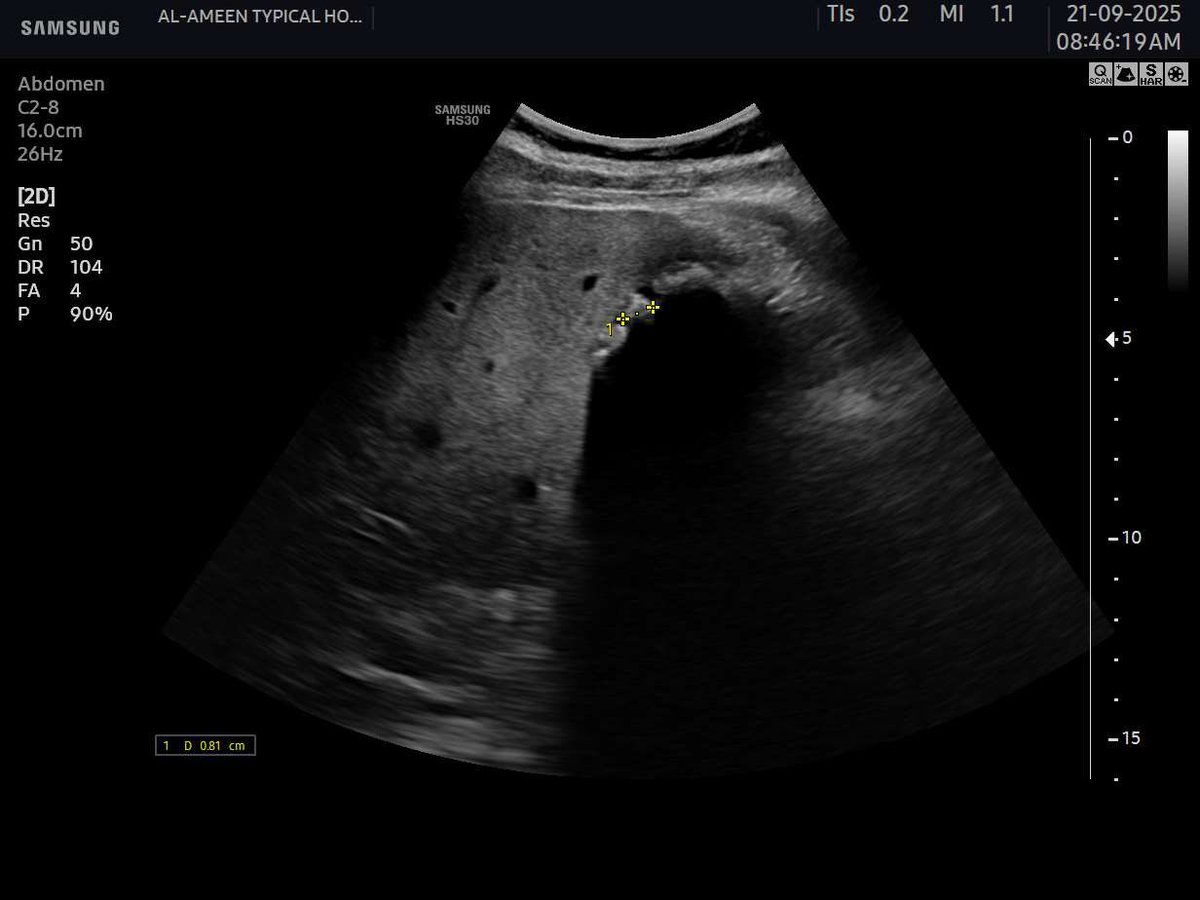

This 50 years female pt came with acute pain in the epigastrium and jaundice. Your opinion? Name of the sonographic sign?? Area of scan :RUQ. #EchoTech

This 50 years female pt came with acute pain in the epigastrium and jaundice. Your opinion? Name of the sonographic sign?? Area of scan :RUQ. #EchoTech